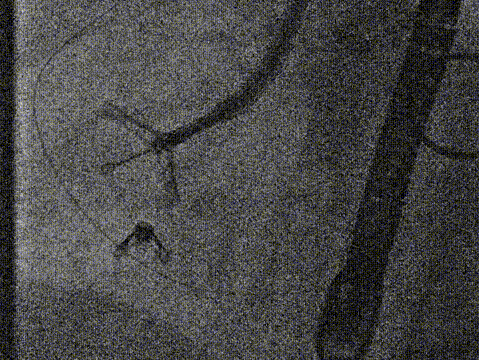

2. Optimal fluoroscopic projection: short-axis view of tricuspid valve, LAO 57°, CAU 11°.

After the patient was placed under general anesthesia, the jugular vein was punctured intraoperatively to establish access. An 18Fr delivery sheath was advanced along the stiff guidewire to the mid‑inferior right atrium. Under ultrasound guidance, the delivery system was introduced, and the angle between the device and the annulus plane was adjusted by catheter deflection and rotation, directing the tip of the clip device toward the target area.

First Clip: 14T clip at the posteroseptal commissure. Due to redundancy of the posterior leaflet hinge region with risk of perforation, the anchor was placed slightly toward the atrial side.

Delivery system entering RA via SCV

Opening clip arms, adjusting orientation, and apposing to the annulus

Retracting tissue, closing clip arms